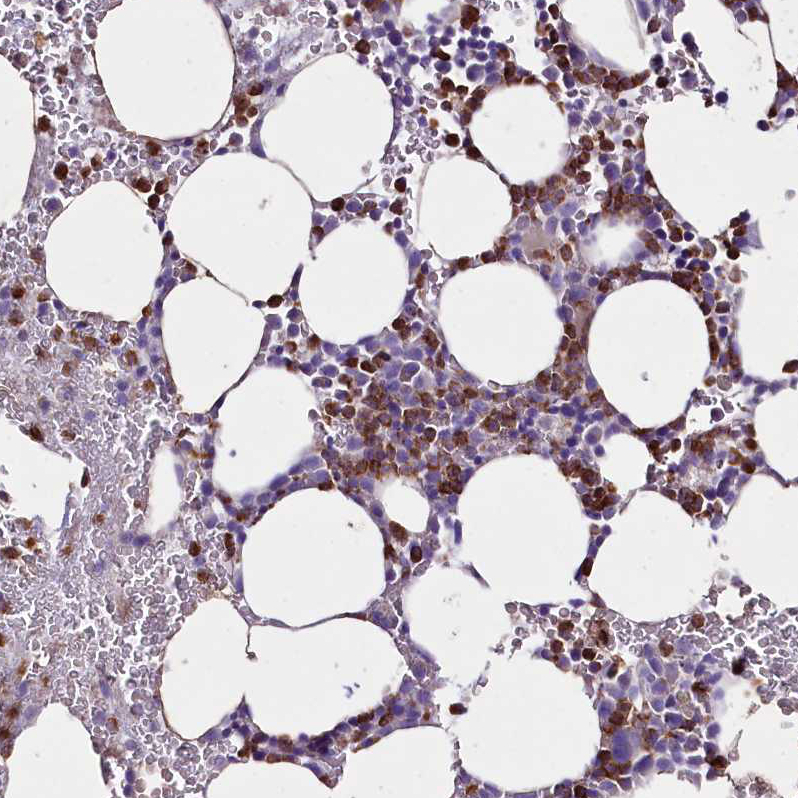

Immunohistochemistry analysis in human testis and endometrium tissues using HPA042144 antibody. Corresponding FAM209B RNA-seq data are presented for the same tissues.